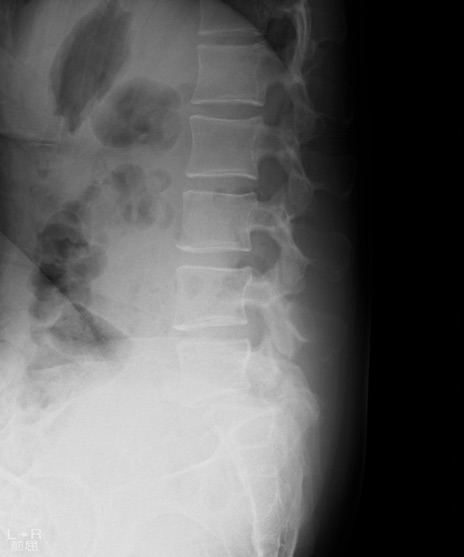

【整形】TIPS症例4 腰椎レントゲン 側面像(屈曲位)

【症例】30歳代男性

【主訴】腰痛、両大腿後面の痛み

【現病歴】高校時代に●●を指摘されたが経過観察されてきた。体動時の腰痛があり、長時間立位、坐位にて両大腿後面の痛みを感じる。外来にて経過観察されてきたが改善ない。

【身体所見】SLR 60/60、TA5/5,EHL 5/5,FHL 5/5、psoas 5/5、quad 5/5、PTR+/+、ATR+/+、babinski-/-、長時間歩行で症状あるがなんとか歩いている。安静時痛なし。体動時、長時間立位、坐位にて症状あり。

異常所見と診断は?